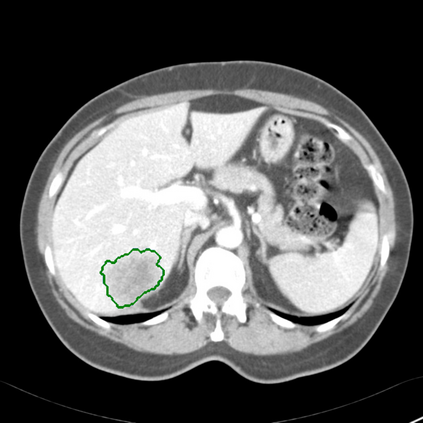

Radiomics uses quantitative medical imaging features to predict clinical outcomes. Currently, in a new clinical application, finding the optimal radiomics method out of the wide range of available options has to be done manually through a heuristic trial-and-error process. In this study we propose a framework for automatically optimizing the construction of radiomics workflows per application. To this end, we formulate radiomics as a modular workflow and include a large collection of common algorithms for each component. To optimize the workflow per application, we employ automated machine learning using a random search and ensembling. We evaluate our method in twelve different clinical applications, resulting in the following area under the curves: 1) liposarcoma (0.83); 2) desmoid-type fibromatosis (0.82); 3) primary liver tumors (0.80); 4) gastrointestinal stromal tumors (0.77); 5) colorectal liver metastases (0.61); 6) melanoma metastases (0.45); 7) hepatocellular carcinoma (0.75); 8) mesenteric fibrosis (0.80); 9) prostate cancer (0.72); 10) glioma (0.71); 11) Alzheimer's disease (0.87); and 12) head and neck cancer (0.84). We show that our framework has a competitive performance compared human experts, outperforms a radiomics baseline, and performs similar or superior to Bayesian optimization and more advanced ensemble approaches. Concluding, our method fully automatically optimizes the construction of radiomics workflows, thereby streamlining the search for radiomics biomarkers in new applications. To facilitate reproducibility and future research, we publicly release six datasets, the software implementation of our framework, and the code to reproduce this study.

翻译:放射科使用定量医学成像特征来预测临床结果。目前,在一个新的临床应用中,通过一个超常试验和高压过程,通过人工操作,从广泛的现有选项中找到最佳放射法。在本研究中,我们提议了一个框架,自动优化每个应用程序的放射工作流程的建设。为此,我们将放射作为模块工作流程,并包括每个部件的大量通用算法。为了优化每个应用程序的工作流程,我们使用随机搜索和聚合的自动机学习方法。我们用12种不同的临床应用来评估我们的方法,结果在曲线下应用的以下领域:1) 脂色瘤(0.83);2) 脱氧型纤维瘤(0.82);3 初级肝脏肿瘤(0.80);4 气肠肿瘤(0.77)、5 彩虹肝脏移植(0.61); 6 脑膜细胞变异常(0.45); 7) 肝细胞变异常(0.8) 脑纤维变异位(0.80); 9) 直径直线型癌症(0.74) 和头型癌症(0.77) 直径研究(10) 。